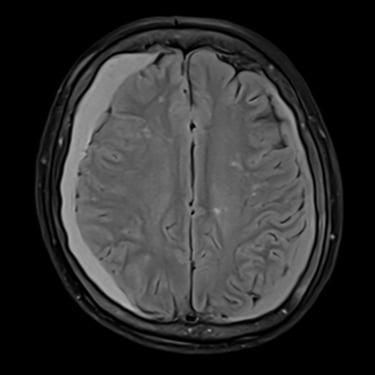

Hematoma Subdural Crónico | Diagnóstico por Resonancia Magnética

El hematoma subdural crónico es una acumulación lenta de sangre entre la duramadre y la superficie cerebral, generalmente secundaria a traumatismos leves en pacientes mayores o anticoagulados. Sus síntomas pueden incluir cefalea persistente, debilidad, alteraciones del lenguaje o cambios en el comportamiento. La resonancia magnética cerebral permite identificar con precisión la extensión y la antigüedad del sangrado, diferenciándolo de otras lesiones intracraneales. Este estudio es esencial para planificar el tratamiento, que puede requerir drenaje quirúrgico mediante trepanación o craneotomía mínima, permitiendo la recuperación neurológica progresiva y reduciendo el riesgo de recurrencia.